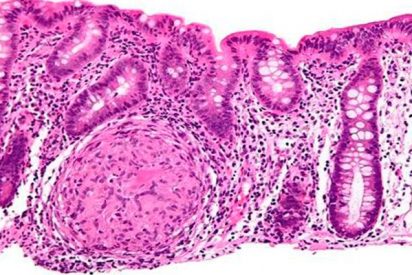

Piden explicaciones por la falta de implantación del cribado del cáncer de colon

El Grupo Parlamentario de Ciudadanos ha registrado esta semana una batería de preguntas en el Congreso de los Diputados con las que pide al Gobierno que explique la falta de implantación del cribado de cáncer de colon en varios territorios autonómicos, pese a tratarse de una prestación obligatoria en todo el Sistema Nacional de Salud (SNS). La formación 'naranja'